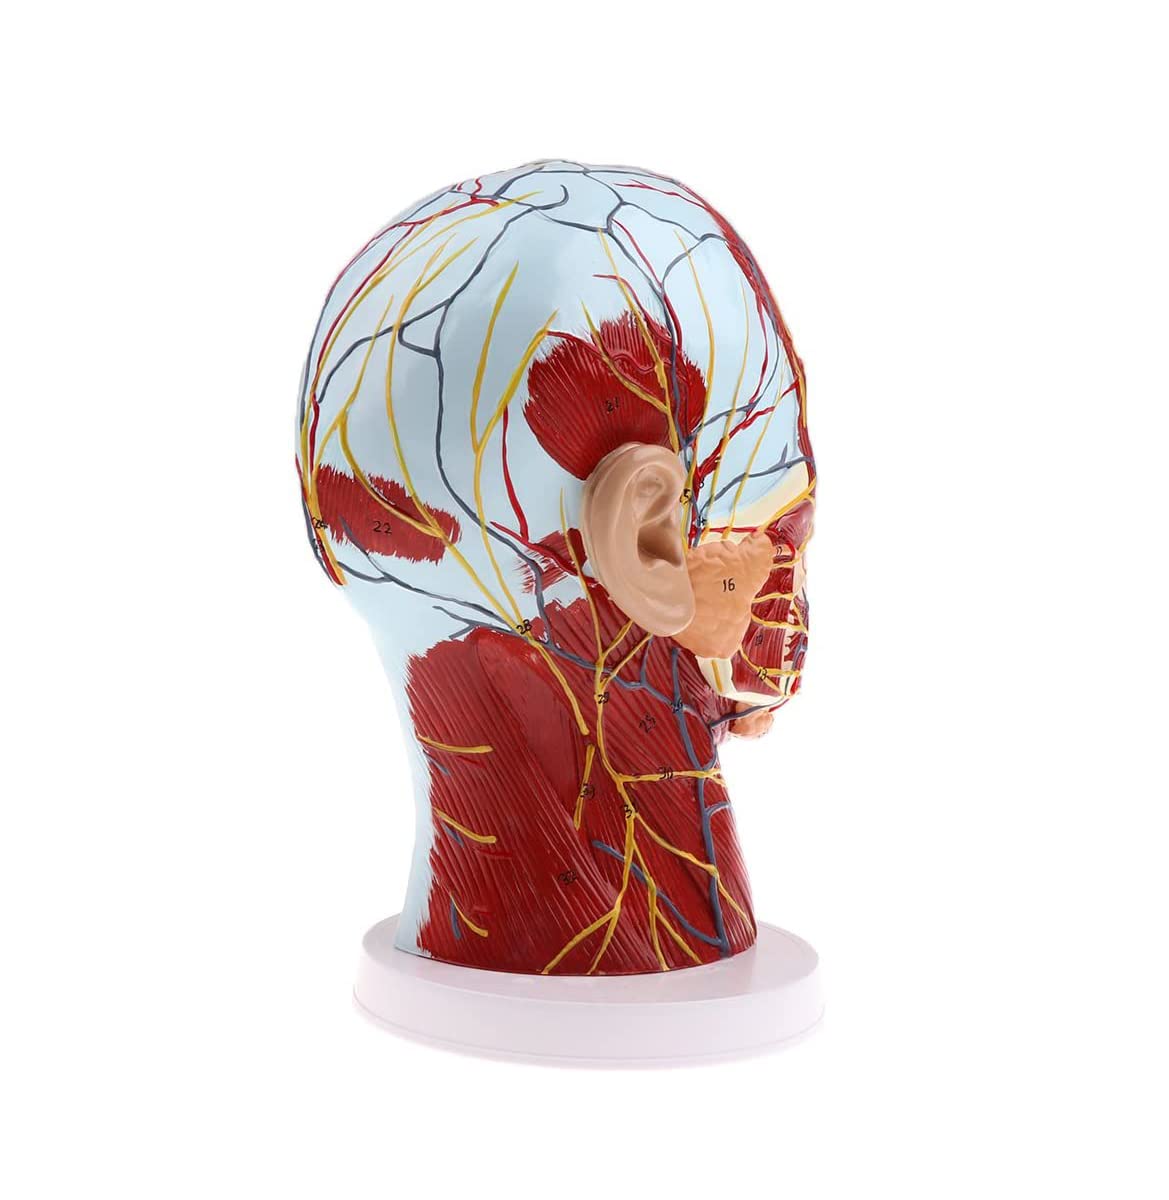

Description:A natural lifesize superficial neurovascular muscle modelMaterial: PVC, PC programmed advanced paintingHighly accurate 3D printing and spatial structureShows details of the human right head and neck and median sagittal plane, including exposed superficial muscles of face, superficial blood vessels, nerves, and parotids of face and scalp, the inner structure of the upper respiratory tract and the sagittal section of cervical spineSuitable for teaching, display, presentation and demonstration in hospital and aesthetic field.Specification:Size: 27 x 21 x 21.5 cm/ 10.6 x 8.3 x 8.5 inchPackage Includes:1 Piece brain model